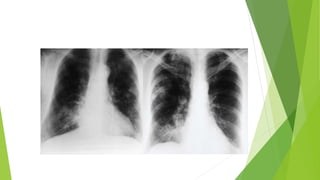

Broncograma Aéreo:  Elbroncograma es uno de los signos frecuentes en las neumonías, pero cuando no existe, no es excluyente de patología alveolar, pues el bronquio puede estar opacificado por estar lleno de detritos o existir otras circunstancias(agenesia bronquial congénita)

Signo del BroncogramaAéreo:  Edema agudo de pulmón

Signo del BroncogramaAéreo:  Infarto Pulmonar

Broncograma Aéreo:  Síndromede Distres respiratorio del adulto: